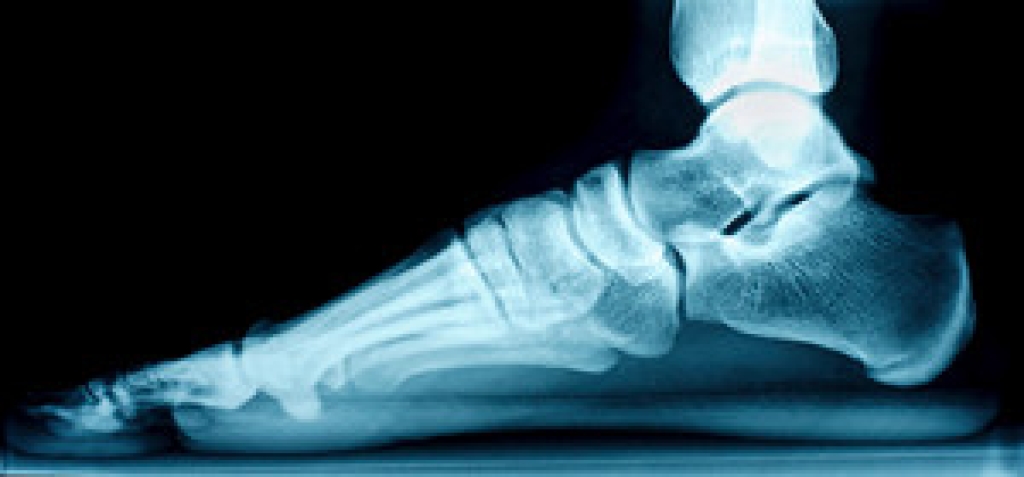

What Are Flat Feet?

Flatfoot is a condition in which the arch of the foot is depressed and the sole of the foot is almost completely in contact with the ground. About 20-30% of the population generally has flat feet because their arches never formed during growth.

- Flat look to one or both feet